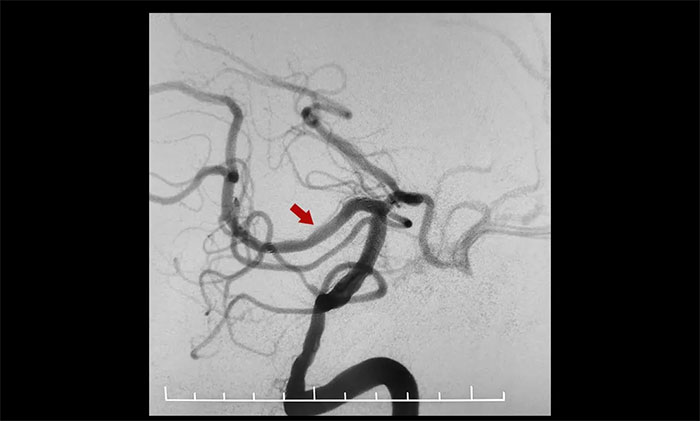

術(shù)中,通過輸送型球囊擴張微導管輕松越過狹窄病變,完成右側(cè)大腦后動脈狹窄段的球囊擴張及支架置入等步驟,無需進行微導管交換、球囊交換以及支架微導管交換的過程。手術(shù)治療部分僅耗時30分鐘。術(shù)后造影顯示右側(cè)大腦后動脈P1、P2交界段重度狹窄明顯改善。行支架CT見支架成形良好。

▲ 術(shù)后,右側(cè)大腦后動脈狹窄明顯改善